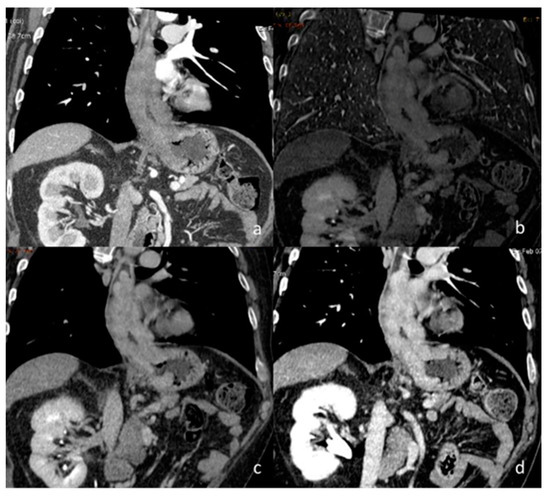

- Si-Mohamed, S.; Dupuis, N.; Tatard-Leitman, V.; Rotzinger, D.; Boccalini, S.; Dion, M.; Vlassenbroek, A.; Coulon, P.; Yagil, Y.; Shapira, N.; et al. Virtual versus true non-contrast dual-energy CT imaging for the diagnosis of aortic intramural hematoma. Eur. Radiol. 2019, 29, 6762–6771. [Google Scholar] [CrossRef] [PubMed]

- Flors, L.; Leiva-Salinas, C.; Norton, P.T.; Patrie, J.T.; Hagspiel, K.D. Endoleak Detection After Endovascular Repair of Thoracic Aortic Aneurysm Using Dual-Source Dual-Energy CT: Suitable Scanning Protocols and Potential Radiation Dose Reduction. AJR Am. J. Roentgenol. 2013, 200, 451–460. [Google Scholar] [CrossRef]

- Shuman, W.P.; O’Malley, R.B.; Busey, J.M. Prospective comparison of dual-energy CT aortography using 70% reduced iodine dose versus single-energy CT aortography using standard iodine dose in the same patient. Abdom. Radiol. 2017, 42, 759–765. [Google Scholar] [CrossRef] [PubMed]

- Huang, F.; Wu, H.; Lai, Q.-Q.; Ke, X.-T. Application value of preoperative dual-source computed tomography in assessing the rupture site of thoracic aortic dissection. J. Cardiothorac. Surg. 2021, 16, 346. [Google Scholar] [CrossRef] [PubMed]

| Si-Mohamed et al. [67] Retrospective study | France | To assess whether VNC images derived from contrast dual-layer DECT images could replace TNC images for aortic intramural hematoma diagnosis in acute aortic syndrome imaging protocols by performing quantitative as well as qualitative phantom and clinical studies. | 21 | IQon, Philips Healthcare No C.I. | Dual-layer -DECT offers similar performances with VNC and TNC images for intramural hematoma diagnosis without compromise in diagnostic image quality. VNC imaging with dual-layer DECT reduces the number of acquisitions and radiation exposure in acute aortic syndrome imaging protocol. |

| Flors et al. [71] Retrospective study | USA | To evaluate the diagnostic performance of dual-source DECT in the detection of endoleaks after thoracic endovascular aortic repair for thoracic aortic aneurysm and to investigate if a double-phase (arterial and dual-energy late delayed phase) or a single-phase (dual-energy late delayed phase) acquisition can replace the standard triphasic protocol | 48 | Somatom Definition, Siemens Healthcare No C.I. | VNC and late delayed phase images reconstructed from a single DECT acquisition can replace the standard triphasic protocol in follow-up examinations after thoracic endovascular aortic repair, thereby providing a significant dose reduction. |

| Shuman et al. [72] Prospective study | USA | To compare DECT aortography using a 70% reduced iodine dose to single-energy CT aortography using a standard iodine dose in the same patient | 21 | Discovery CT750 HD; GE Healthcare, Waukesha, WI) One author received research grants from GE Healthcare No C.I. | 70% reduced iodine DECT aortography may result in similar aortic attenuation, CNR, SNR, and lower although acceptable subjective image scores when compared to standard iodine single-energy aortography in the same patient. |